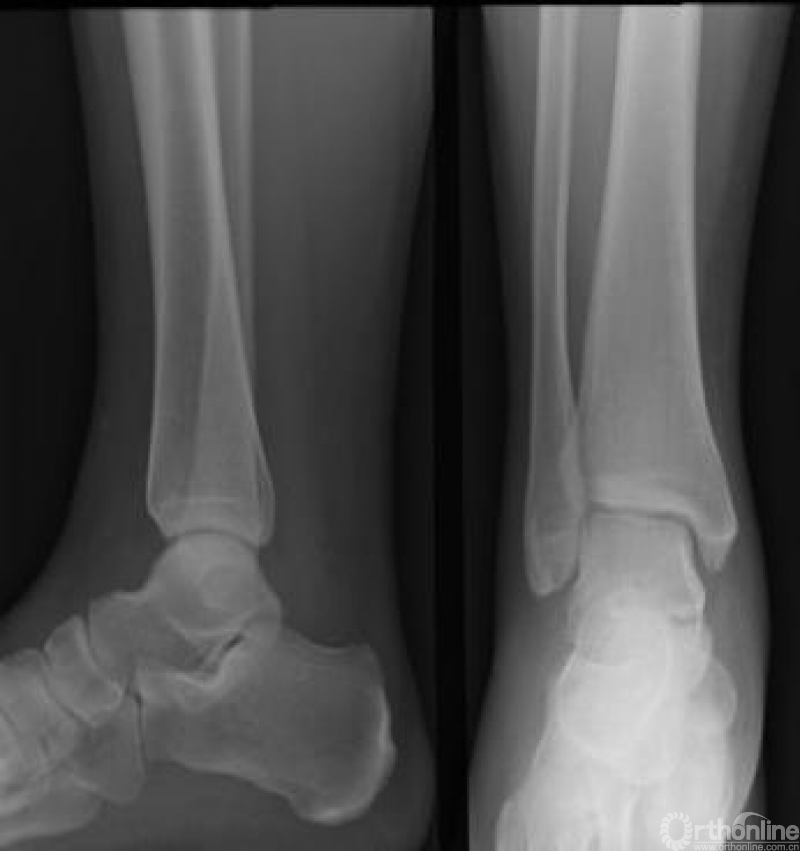

众所周知,本届冬奥会贾宗洋是带伤参赛。相信大家都看过这张X线片,这是贾宗洋左腿受伤术后的片子,整整打了22根钢钉。

原来,贾宗洋在备战2018年平昌冬奥会期间,高强度的训练使他意外出现左小腿骨折。从片子上来看,诊断应该是左胫腓骨远端粉碎性骨折,左踝关节骨折。

胫腓骨远端肌肉附着少,大切口会影响血运,容易出现骨不连、骨感染等并发症,因而贾宗洋的手术采用微创术式,尽量的减少和缩小切口。术中采用生物学固定理念做的钢板内固定手术,同时选用配合微创切口使用的解剖钢板进行固定。因为只有采用微创生物学固定的原则,才能为患者早期功能锻炼和早期康复创造条件。

此外,作为关节内骨折的踝关节骨折,术中也需要尽量达到解剖复位,在手术成功的同时,贾宗洋术后还需要刻苦的功能锻炼,才能获得一个良好的踝关节功能,赶上当年的奥运会并获得好成绩。说完贾宗洋的故事,下面我们重点聊一聊“踝关节骨折”的诊疗。

踝关节受损伤后存在压痛点或者不能够负重是行X线检查的最佳适应证。X线检查可观察有无骨折和关节间隙的改变。踝关节常规照片包括前后位、侧位以及内旋位X线片(图1)。

图1 正常踝关节正、侧位X线片